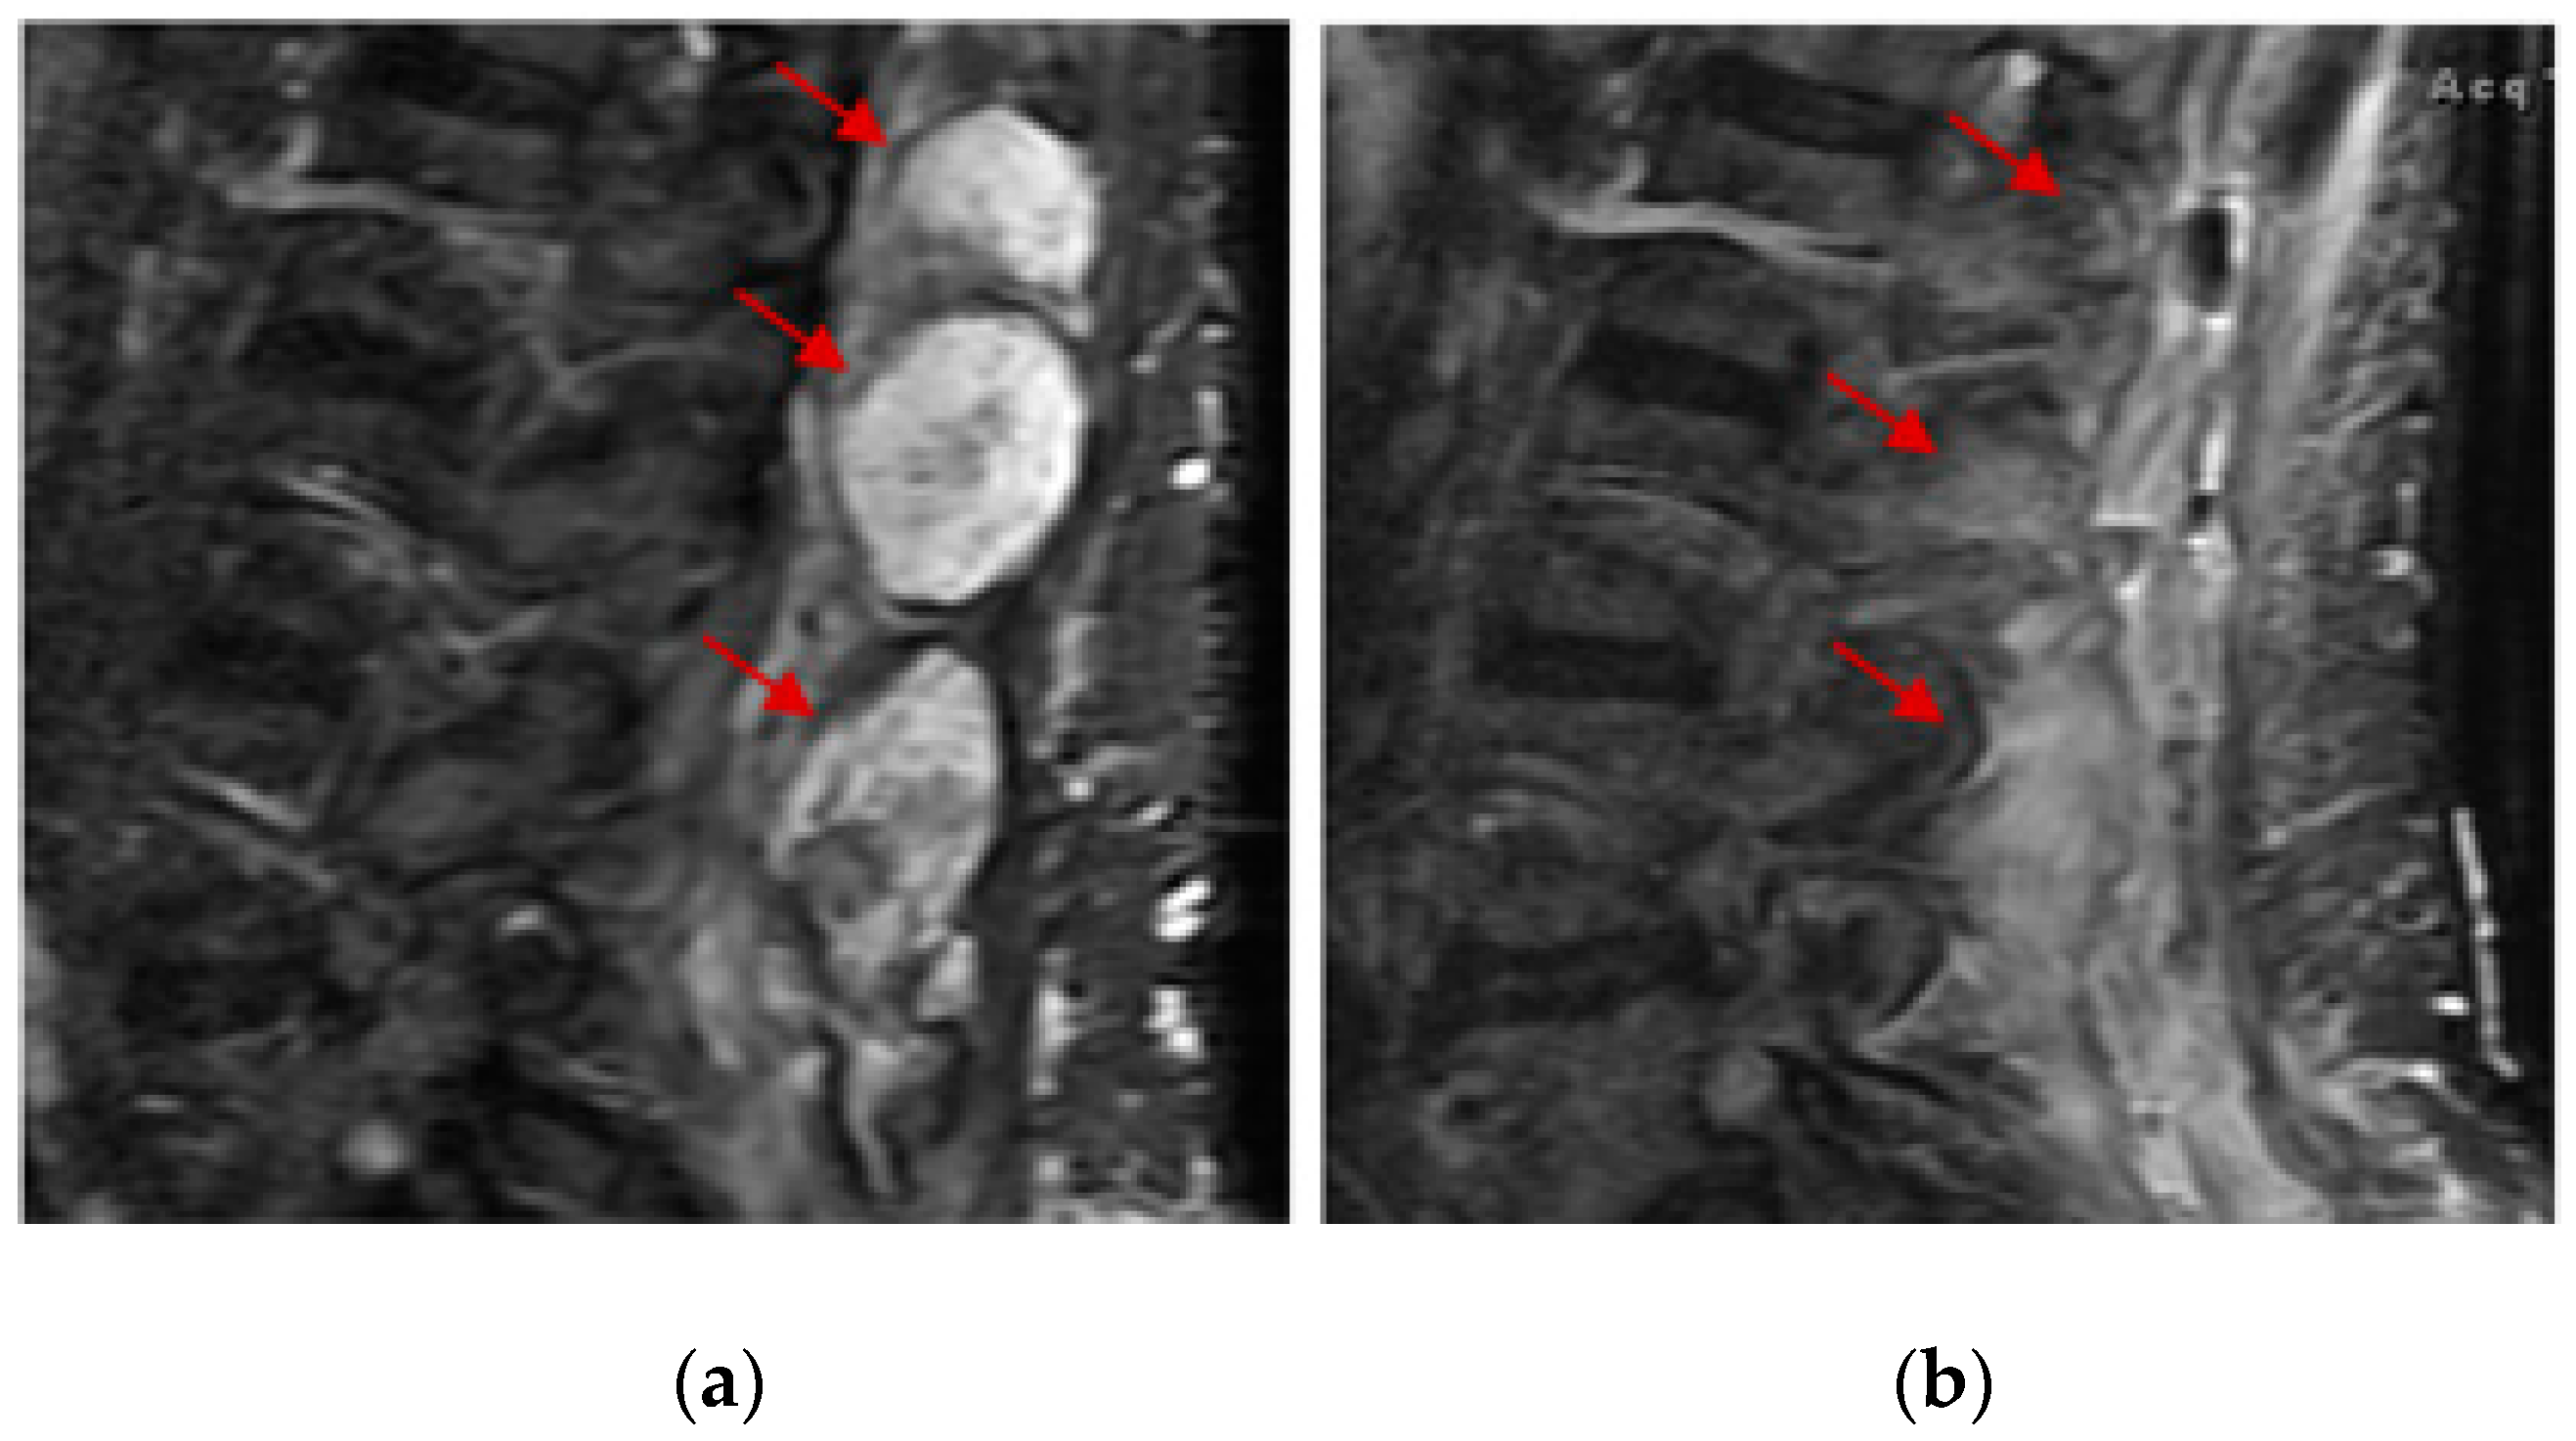

- Mori, Y.; Kinoshita, S.; Kanamori, T.; Kataoka, H.; Joh, T.; Iida, S.; Takemoto, M.; Kondo, M.; Kuroda, J.; Komatsu, H. The Successful Treatment of Metastatic Extraosseous Ewing Sarcoma with Pazopanib. Intern. Med. 2018, 57, 2753–2757. [Google Scholar] [CrossRef]